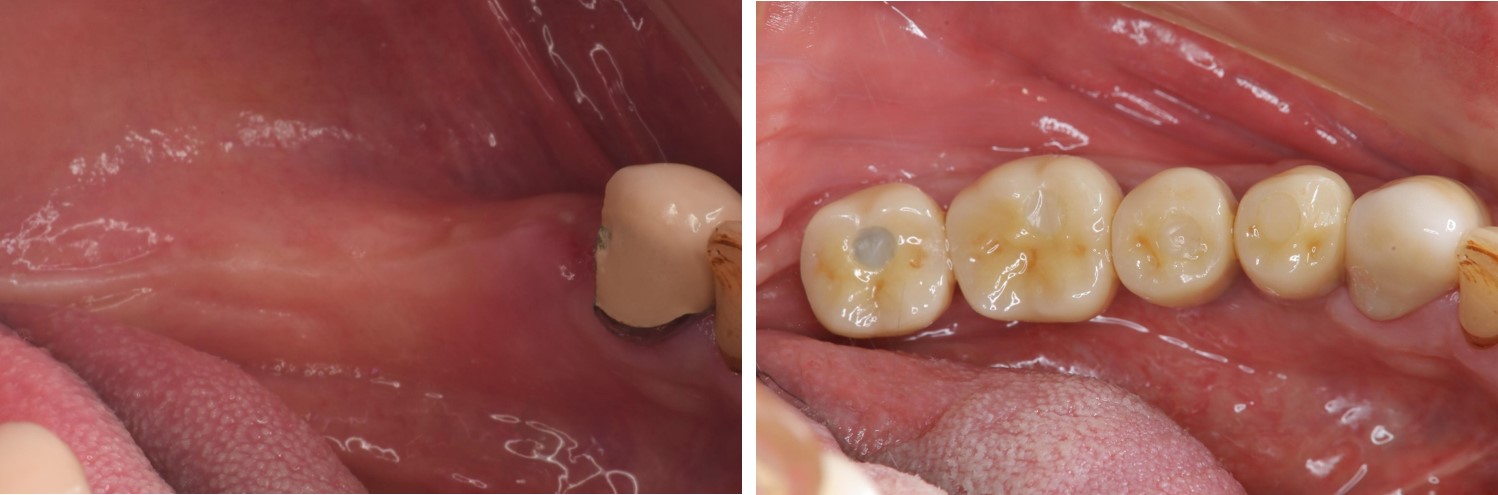

▲(治療前,左下顎缺牙,咬合喪失)

治療前,左下顎缺牙,咬合喪失

治療後,口內照(終於!我家人的牙齒回來了,雖然看不太習慣,但我家人說她終於找回當年有牙齒的感覺了~果然缺牙還是口腔有問題,找醫生就對了,一般人哪可能自己生出牙齒來!)

治療後,口內照